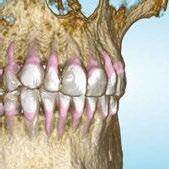

When treating patients with severe crowding in both arches, a traditional orthodontic treatment approach can lead the orthodontist to recommend an extraction strategy. Once an extraction approach is considered, the provider will need to further determine which extraction pattern or strategic extraction pattern is best for the individual patient. Extraction of the first premolars is a commonly utilized extraction pattern in cases with moderate-to-severe crowding with adequate posterior anchorage to allow for proper de-crowding of the arches. However, one important additional consideration may reroute the traditional treatment approach — are there currently any teeth with compromised alveolar support that may be a better candidate for extraction instead of a healthy first premolar? Consider a case involving severe mandibular anterior crowding with a lower incisor that appears to be dehisced outside the bounds of stable alveolar support. A CBCT X-ray image allows one to not only carry out a very accurate space analysis, but also assess each tooth individually with regard to possible compromised alveolar support. If an orthodontist were to see on a CBCT X-ray image that the lower incisor in question was entirely beyond the facial cortical plate, would he/she reconsider extracting premolars in favor of the questionable incisor?

CBCT adds another consideration to the pretreatment evaluation and can help the orthodontist develop a more strategic extraction pattern. In other words, the additional information provided by CBCT can provide visual confirmation that could influence the treatment plan. When “strategic extraction” is mentioned in orthodontics, it usually relates to anchorage requirements. CBCT can add additional information that could help to improve how cases are treated.

It was clear that extractions were going to be necessary to relieve crowding for this patient. It was unclear which mandibular teeth would be best suited for extraction, considering that tooth Nos. 24, 26, and 27 were ectopic and considerably displaced out from the center of the alveolar housing or trough (Figure 2B). Additionally, tooth No. 24 was already showing signs of gingival recession (Figure 2D), further suggesting its position within the alveolar housing was compromised.

The CBCT image revealed several findings. First, it was apparent that a periapical radiolucency (PARL) existed in association with the overlapping mandibular incisors (Figures 4A – 4C). Figure 4A shows tooth No. 24 with compromised facial alveolar support, while figure 4C shows tooth No. 25 with a greater amount of visible facial bone. In figure 4E, tooth No. 27 is proclined and has compromised facial alveolar support. Lastly, a second PARL was noted surrounding tooth No. 8 (Figure 5).